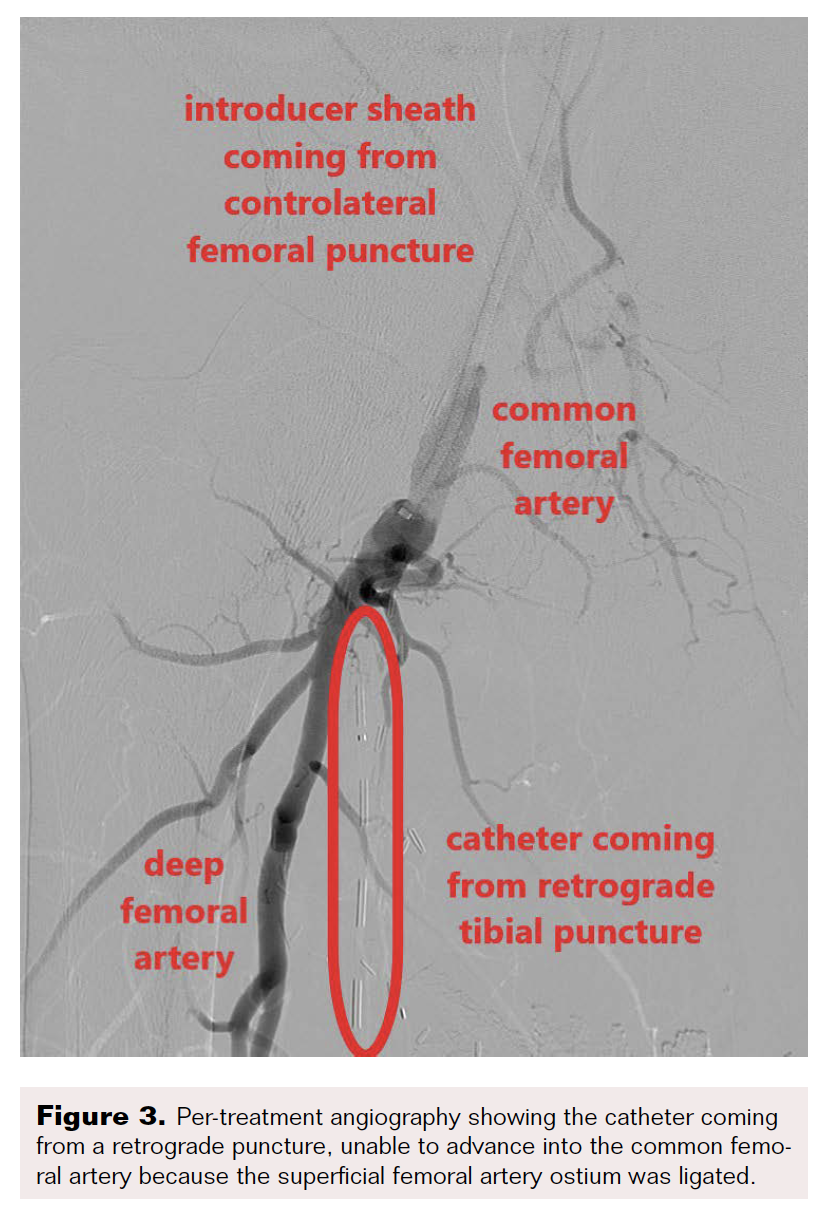

Computed tomography angiography highlighted thrombosis of the femoroposterior tibial bypass and a grade 4 Global Limb Anatomic Staging System femoropopliteal and tibioperoneal trunk chronic total occlusion (CTO). Runoff vessels were patent (Figure 2). Through retrograde posterior tibial puncture, we tried to recanalize the CTO but were not able to get into the common femoral artery (CFA) because the SFA ostium was ligated (Figure 3). We performed a short Dacron prosthetic bypass between the CFA and the proximal part of the SFA (Figure 4), followed by stenting of the whole SFA and the proximal third of the popliteal artery with drug-eluting stents. The distal part of the popliteal artery and the tibioperoneal trunk were treated with balloon angioplasty.

Revascularization techniques for CLTI are based on 3 points: patient risk, limb severity, and anatomic complexity.8 Extensive multilevel atherosclerotic disease is frequently associated with multiple medical comorbidities, making patients with CLTI at high risk for extensive open surgical procedures.5 Our reported case had multiple bypass surgeries. Percutaneous treatment will not always allow complete revascularization. Thus, a hybrid approach may help revascularize CLTI.9 Our patient needed open surgery because his SFA ostium had been ligated during one of the previous surgeries. The femoropopliteal arterial axis could be recanalized percutaneously.